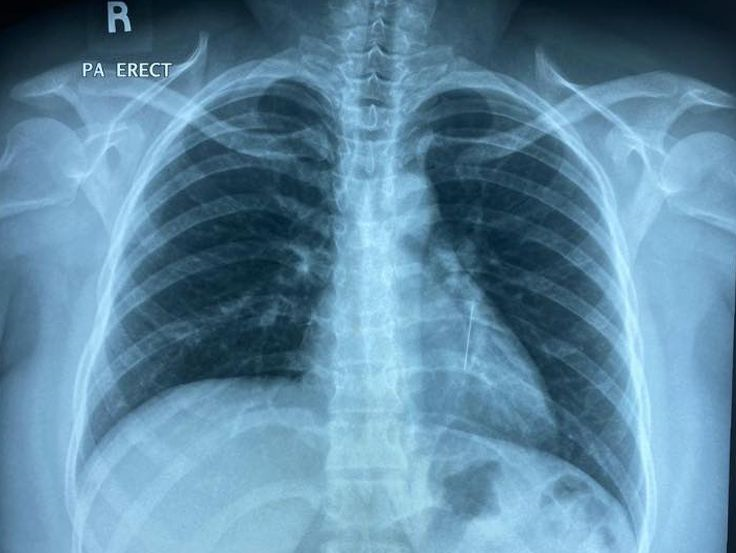

Penyakit respiratori kronik penyakit respiratori kronik adalah penyakit sistem pernafasan yang berlaku apabila terdapat penyempitan dan radang (inflamasi) pada saluran pernafasan. Penyakit hepar kronik merupakan suatu penyakit pada hepar yang melibatkan kerusakan progresif dan regenerasi parenkim hepar foto rontgen : Penyakit kronik ini memberi kesan kepada kualiti kehidupan pesakit dan keluarga pesakit. Tanda yang muncul antara lain : Penyakit paru obstruksi kronik (ppok) adalah penyakit paru kronik yang ditandai oleh hambatan aliran udara disaluran pernapasan 2. Kebanyakan pesakit mengambil sikap tunggu untuk berjumpa doktor sehinggalah batuk mereka menjadi semakin teruk. Jantung tidak normal (detak jantung tidak beraturan) sering terkena infeksi respiratori, termasuk pneumonia gagal. (dialihkan dari penyakit paru obstruktif kronik). Sering terkena infeksi respiratori, termasuk pneumonia. Cor tidak membesar, pulmo tak tampak kelainan v. Ppok (penyakit paru obstruksi kronik) adalah penyakit paru kronik yang ditandai oleh hambatan aliran udara di saluran napas yang bersifat progressif nonreversibel atau reversibel parsial. Tujuan utama dari penatalaksanaan penyakit paru obstruktif kronik (ppok) atau chronic obstructive pulmonary disease (copd) antara lain untuk mengurangi gejala, mencegah eksaserbasi berulang, memperbaiki dan mencegah. Pakar perunding kanan respiratori, institut perubatan respiratori, hospital kuala lumpur (hkl), datuk dr (rainbow across borders bertujuan meningkatkan kualiti hidup para pesakit dan keluarga mereka yang terpaksa berhadapan dengan cabaran penyakit kronik atau yang mengancam nyawa.)